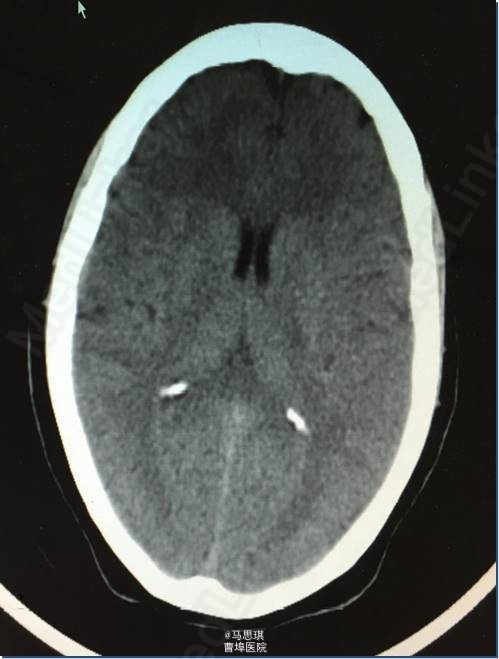

入院诊断为:“脑梗塞?” 患者有溶栓指征,但患者家属拒绝溶栓。 治疗: 氯吡格雷75mg Qd 拜阿司匹林0.1 Qd 立普妥 20mg qd 胞磷胆碱0.2tid 依达拉奉30mg ivgtt bid 康复治疗 入院第二天行MRI及MRA检查。 头部MRI:左侧额颞岛叶见片状稍长T2稍长T1信号灶,其内见较多增粗、增多血管影,原因?考虑:血管畸形所致左侧额颞岛叶缺血梗塞性改变?血管炎性病变或脑炎待排? 头颅MRA:左侧额颞岛叶见较多增粗、增多的血管影,右侧额颞顶交界区血管影稍增多。左侧胚胎型大脑后动脉。 入院第四天行头颅增强CT及CTA。 头颅增强CT:左侧颞叶见片状低密度影,其内见大小约0.7x1.6cm片状高密度影,与前片比较,见范围加大,考虑系梗塞后伴出血,血管畸形。增强扫描见左侧额颞叶较多迂曲扩张的血管影。 CTA:左侧额颞岛叶区域见大脑中动脉岛叶段,侧裂段及分叉段分支明显增多,部分迂曲、扩张,呈杂乱走行的血管团样改变,考虑血管畸形可能;右侧额顶交界区血管影稍增多。双侧颈内和基底动脉及大脑前中后动脉显示清晰,其大小、走行、信号未见确切异常,各血管壁光整,管腔未见确切狭窄,走行自然。 发现出血后,停用双联抗小板治疗,并加做DSA DSA示:左侧颈外动脉分支脑膜中动脉血管畸形,与颈内动脉,椎动脉无明显交通 修正诊断为: 左侧额颞岛叶脑梗塞并梗塞后出血; 左侧脑膜中动脉血管畸形 动脉粥样硬化症 上呼吸道感染

复查CT(3周后):左侧额颞顶叶片状脑梗塞密度较前片略降低。 3周后,患者行左侧脑膜中动脉血管畸形栓塞术,但因患者于部分供血血管造影时述左耳疼痛明显,放弃有明显临床症状供血血管栓塞术,随后出院。嘱氯吡格雷75mg Qd 立普妥 20mg qd 讨论:对于此类特殊病因的卒中患者如何评估溶栓风险?如何评估双抗风险?